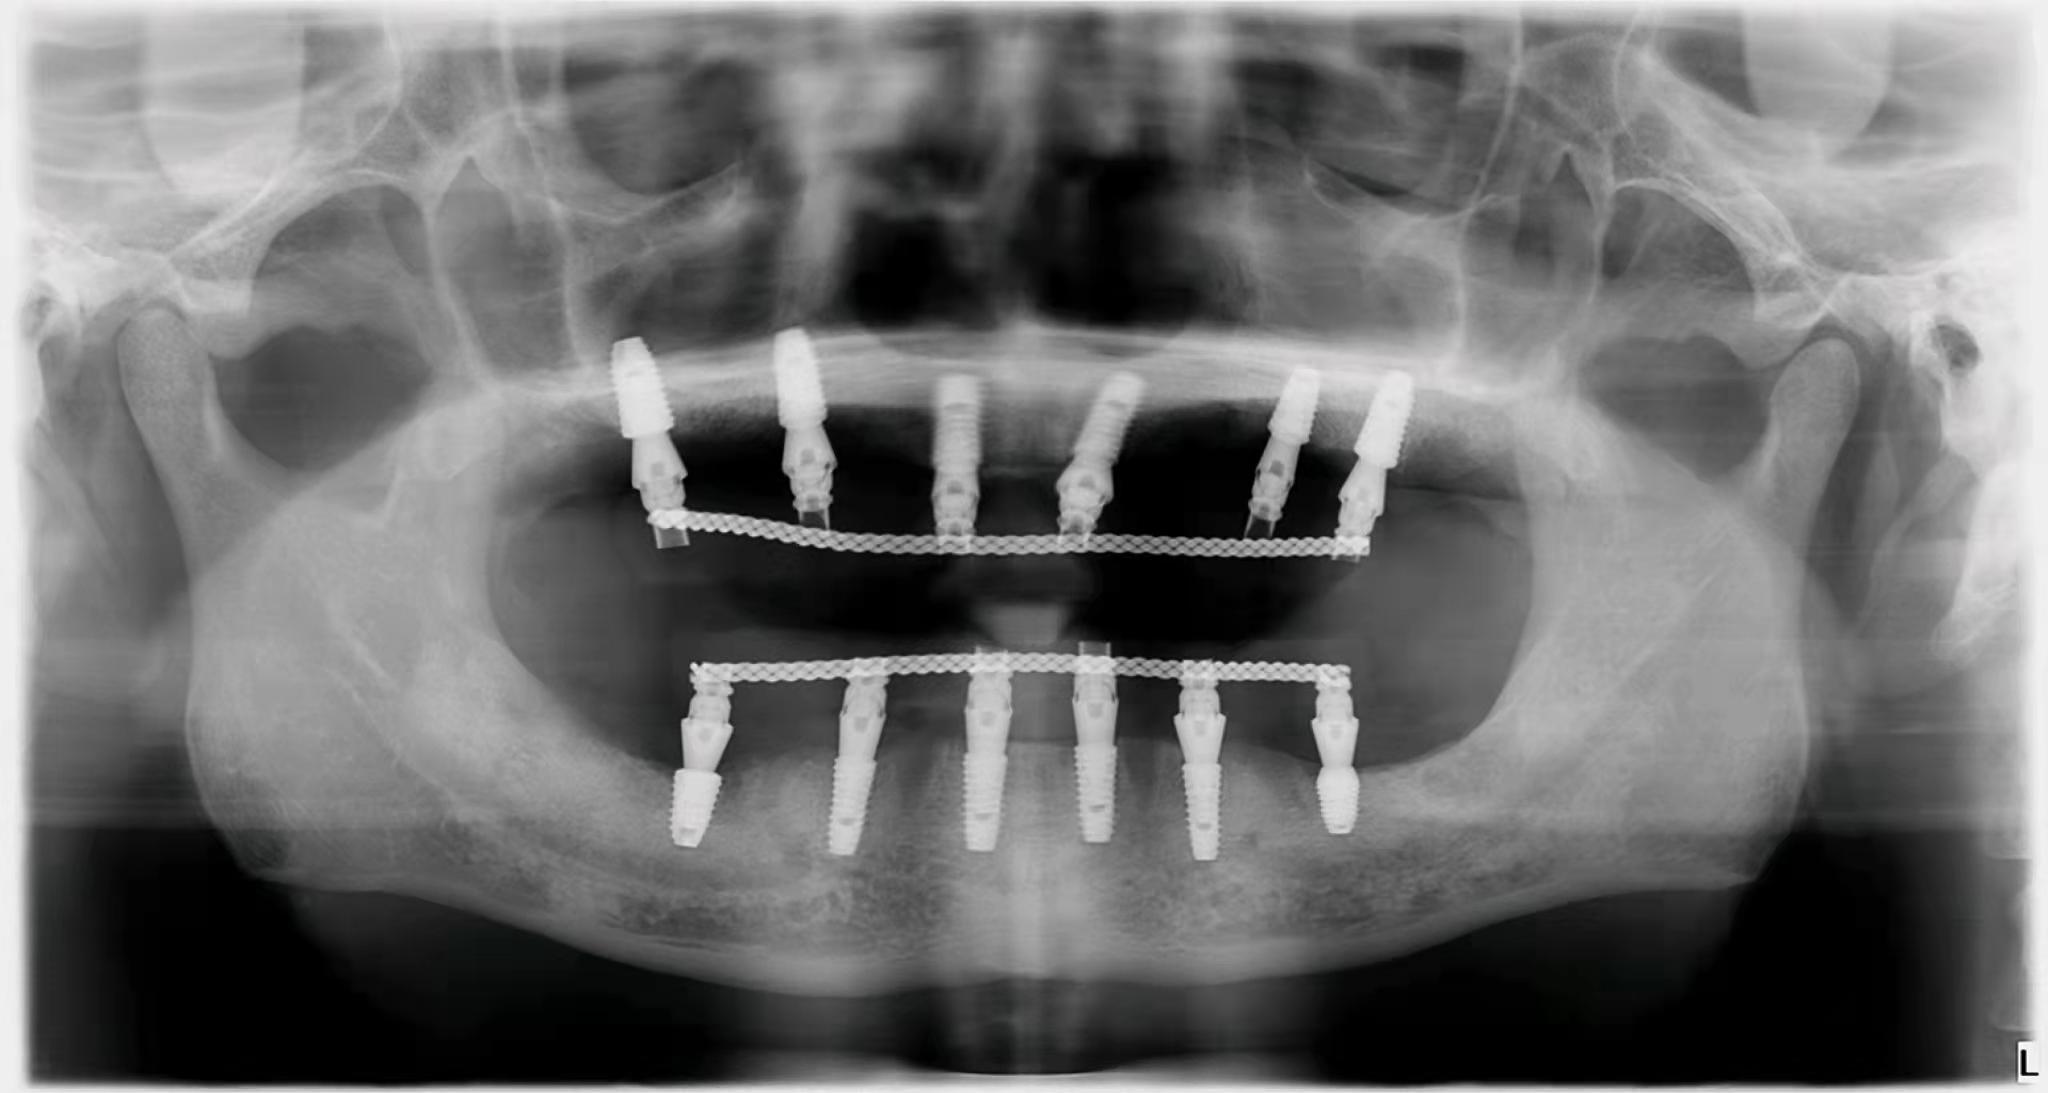

3. 種植牙價格降低在公立和私立口腔中,與種植體不同的是,國內(nèi)部分牙冠品牌已經(jīng)被大眾接受。如果是單顆牙缺失,預(yù)算有限,可以找醫(yī)生咨詢低成本方案。即使是全口或者半口牙缺失,需要種植,也不需要在牙窩上全部種植,可以用all-one-4,或者all-one-6。